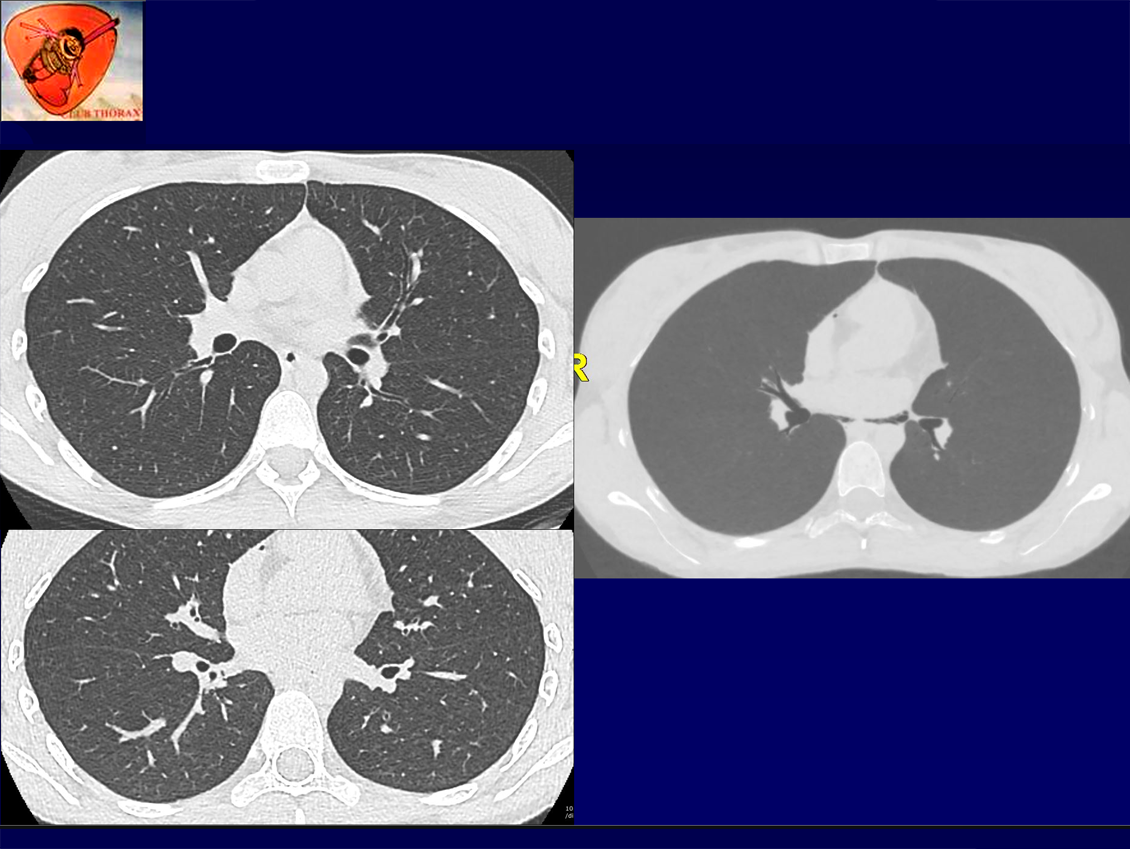

Femme 21ans, Douleur thorax brutale sans dyspnée.

Pas d’antécédent cardiothoracique particulier

Bon état général

Apyrétique

Auscultation: normale

Saturation à l’air ambiant: 98%

Pas de syndrome de MARFAN

QUEL EST VOTRE DIAGNOSTIC ?

A – Pneumopéricarde spontané

B – Pneumothorax

C – Emphysème sous cutané

D – Macklin syndrome

E – Boerhaave’s syndrome